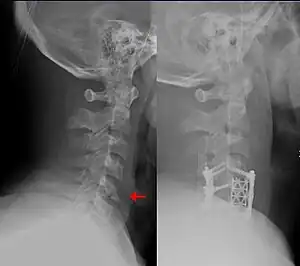

There are multiple devices that can be used in addition to avoiding maneuvers or activities that move the spine.[8][19] Long-term cervical spine immobilization in patients with cervical spine fracture who did not undergo surgery can be performed using a long-term cervical collar (Miami J,[6][8] Philadelphia,[8] or Aspen[8]) or halo traction device.[8][13] When using a traction device such as the halo to hold the spine in place while it heals, this is called closed reduction, as opposed to a surgery which is termed open reduction with internal fixation (ORIF).[19] In general, the halo traction device is preferred for unstable fracture, while the cervical collars are used for neck sprain, stable fracture, or after surgical fixation.[8] Soft cervical collars do not restrict head movement and are more so used for comfort.[8] The sternal occipital mandibular immobilizer (SOMI) can also be used to provide support for cervical spine sprain, stable fracture, or postoperative support.[8]